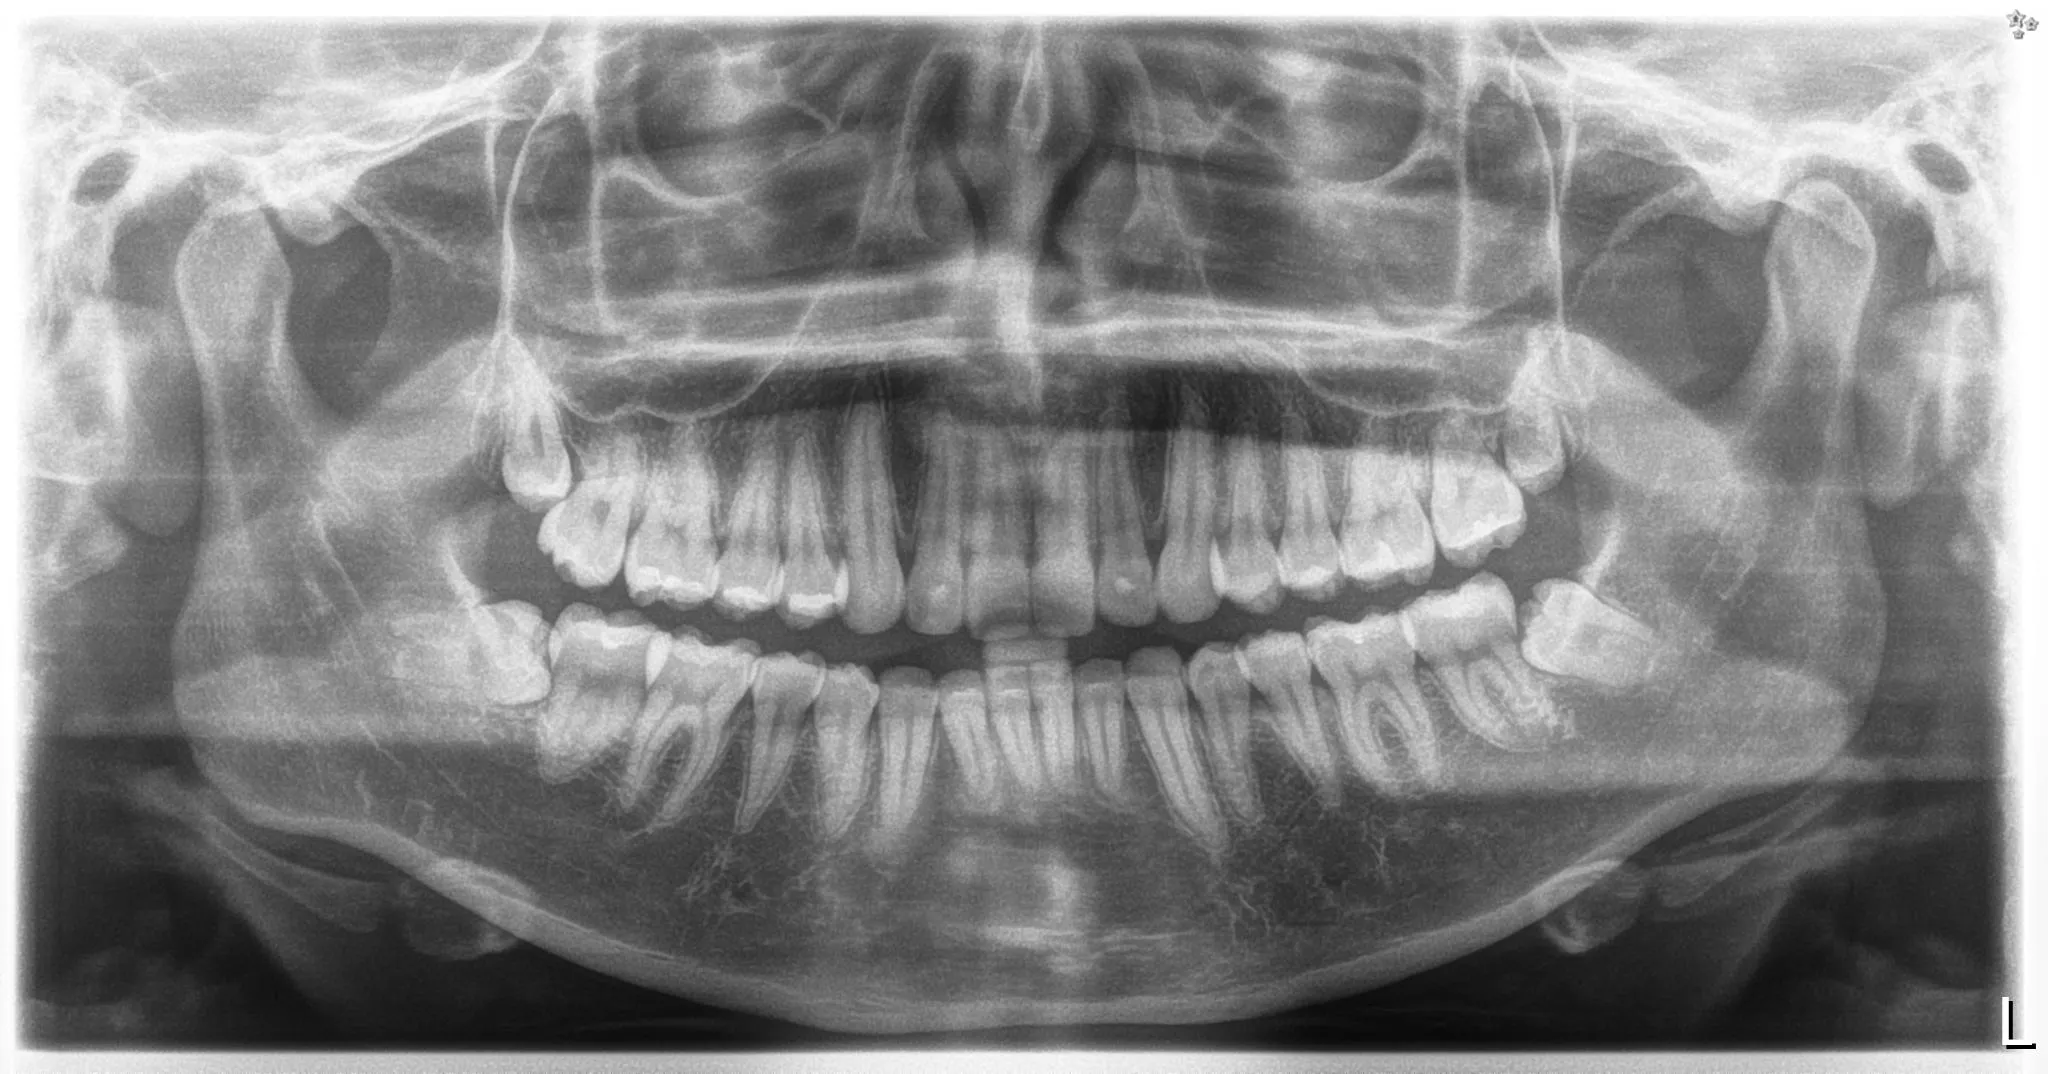

Mediante una radiografía panorámica evaluamos posición, desarrollo radicular, relación con el nervio dentario y posibles afectaciones al molar contiguo. Esto guía la planeación y reduce riesgos.

Radiografía panorámica de tercer molar